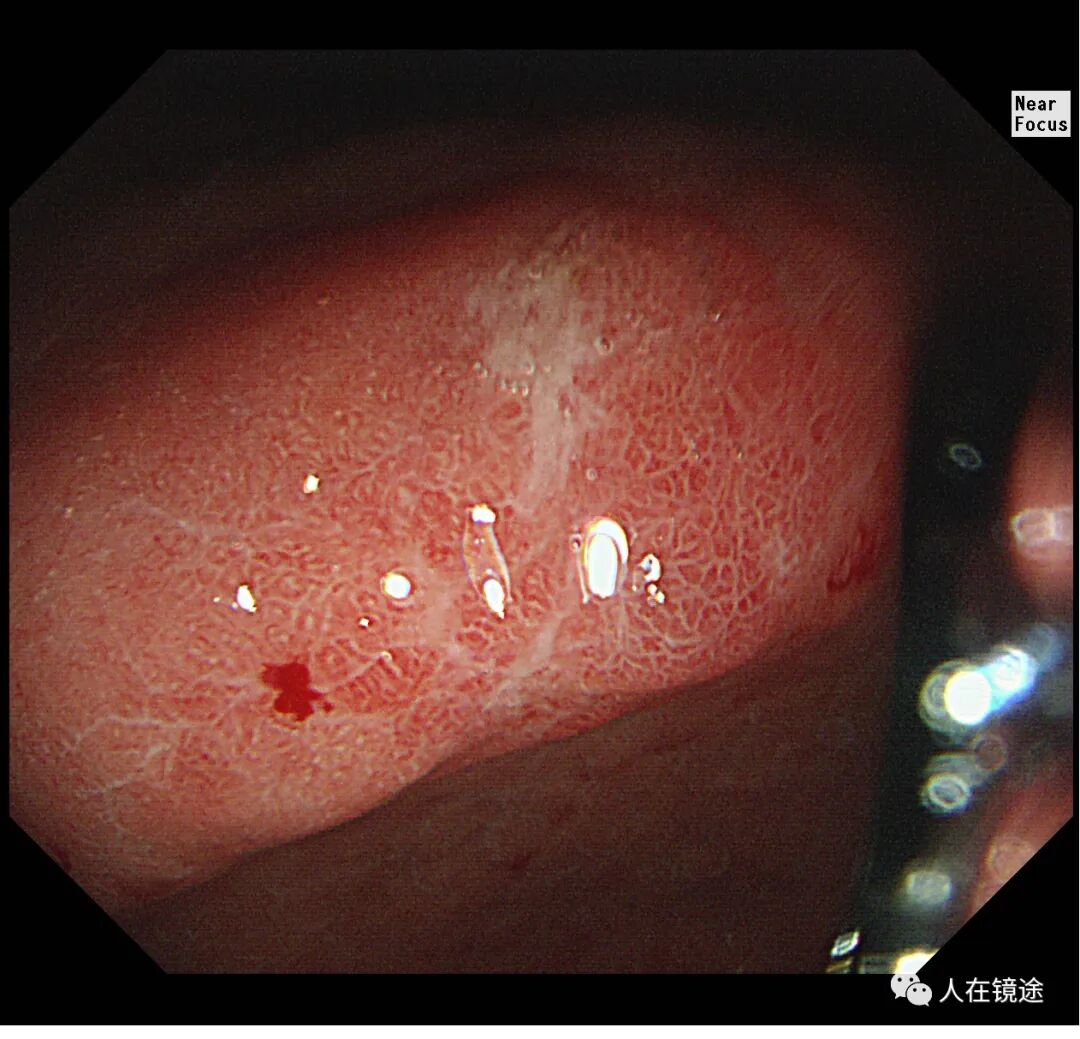

白光+近焦示:胃窦小弯见一0.8*1.2cmIIa粘膜发红病变,微结构稍紊乱,表面粘膜高低不平伴自发性出血。